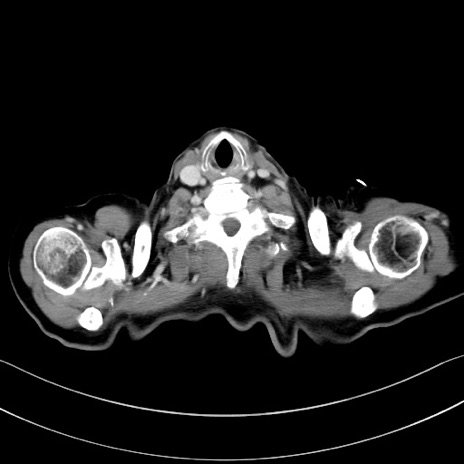

症例28(横断像)

【症例】60歳代男性

【主訴】嘔吐

【現病歴】胃癌にて胃全摘後。食思不振が悪化し、夜中に嘔吐することがある。

【既往歴】胃癌、胃全摘、脾摘、胆摘後

【データ】WBC 5900、CRP 10.56